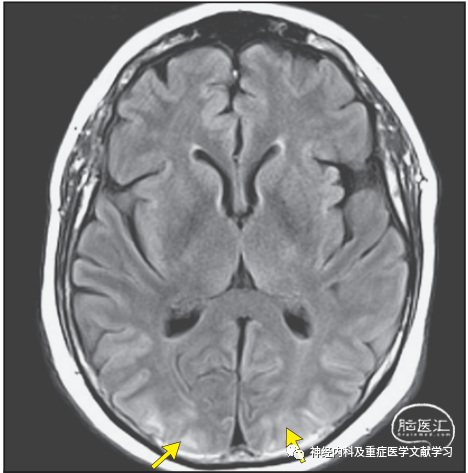

神经影像学是诊断PRES的核心标准。颅脑非增强断层扫描(CT)检查可以发现双侧后循环供血区域明显脑水肿。液体衰减反转恢复和t2加权序列对血管源性水肿更敏感,所以RES影像学诊断磁共振成像(MRI)比CT更准确。MRI信号改变主要发生在双侧枕叶的脑白质区(图1),但也有单侧或灰质受累及其他异常的报道。

58岁男性,急性重度高血压、恶心、呕吐和精神状态改变入院。颅脑磁共振成像(MRI)轴向液体衰减反转恢复(FLAIR)扫描显示主要在双侧枕叶的皮层下和皮层高信号(箭头)。病变区域的弥散加权图像(未示出)正常。颅脑CT可能不像MRI那么明显。